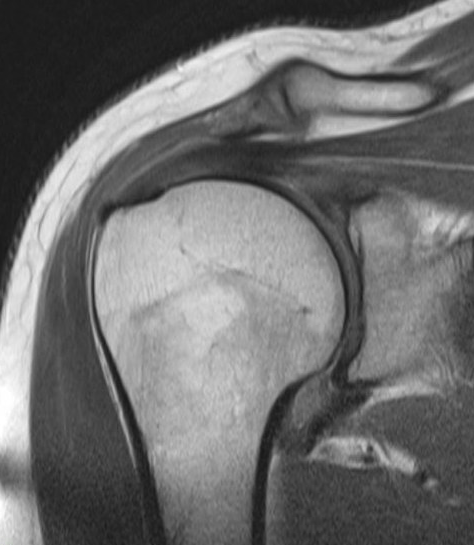

MRI

Thickened capsule and synovitis of axillary capsular recess